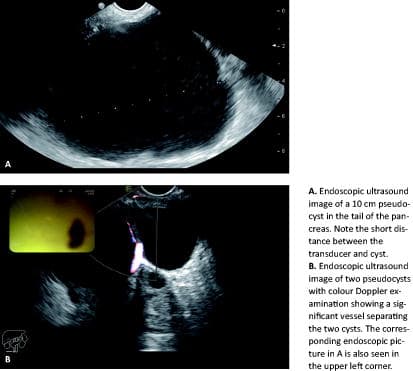

– The PPC and the pancreas were assessed by EUS and the location most suitable for the puncture was selected. Doppler imaging was used to reduce the risk of damaging interposed vessels.

No significant bleeding occurred in the present study. This may be so owing to the use of Doppler imaging to avoid interposed vessels in our study. Some authors have, however, found standard ultrasonic imaging without the use of Doppler to be adequate to secure safe drainage of pseudocysts, even in patients at a high risk of bleeding [12].